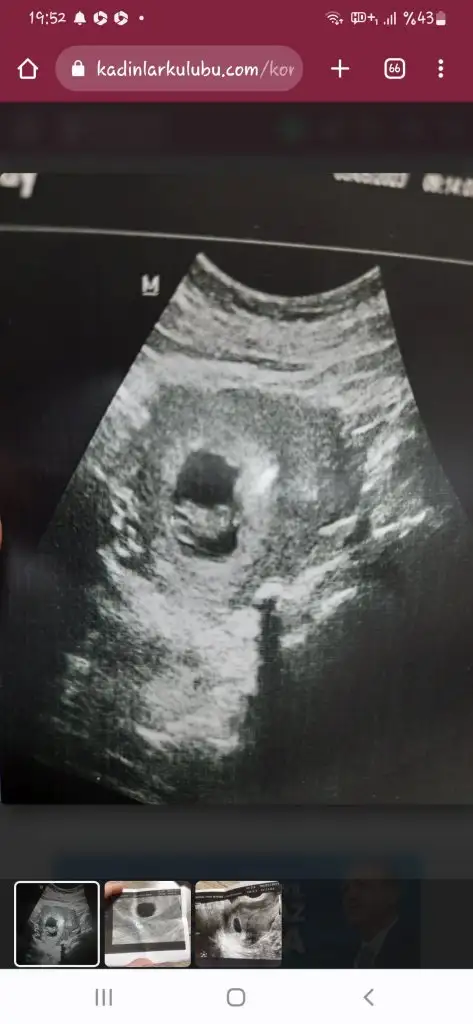

geç döllenme ihtimalin varsa bekle kuzum biraz daha boş gebelik de bebek yok ya anneye zarar vermıyor zaten yine sen daha iyi bilirsin ben olsam beklerdim ki benım gec döllenme ihtimalim yok ona rağmen beklemeyi düsünmüyo değilim kürtaj derlerse bilmiyorum kafam o kadar karısık allak bullak ki doktor 15gün sonra bi daha gel dedi ama tsh yüksek cıktı hemen dahiliye git ilaca basla da dedi diyorum ki olumsuz bisi olsa troid ilacına hemen basla der miydi kiEn azından sana 15 gün daha vermiş benimki hemen kürtaj diyor

Valla bilmiyorum ki tiroid ilacı da kullanılıyor mu ki hamilelikte doktorları da cozemiyorum artikgeç döllenme ihtimalin varsa bekle kuzum biraz daha boş gebelik de bebek yok ya anneye zarar vermıyor zaten yine sen daha iyi bilirsin ben olsam beklerdim ki benım gec döllenme ihtimalim yok ona rağmen beklemeyi düsünmüyo değilim kürtaj derlerse bilmiyorum kafam o kadar karısık allak bullak ki doktor 15gün sonra bi daha gel dedi ama tsh yüksek cıktı hemen dahiliye git ilaca basla da dedi diyorum ki olumsuz bisi olsa troid ilacına hemen basla der miydi ki